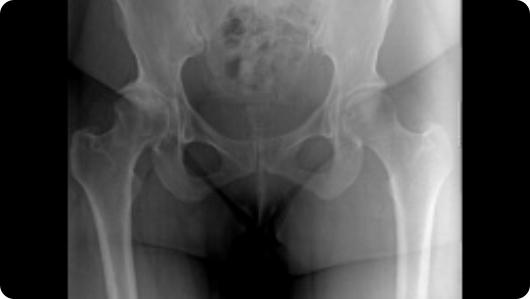

Radiographic image of hip arthritis Radiographic image of a total hip replacement

Hip Arthritis

Total Hip Replacement